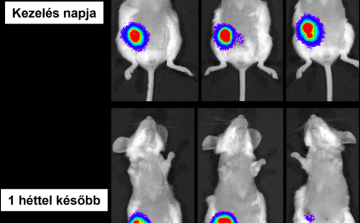

HUN-REN: új lendületet adhat a rák elleni harcnak a magyar kutatók fejlesztése